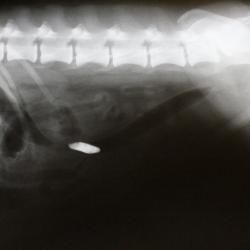

Frede kom ind til os og blev undersøgt, og det viste sig hurtigt, at han skulle have taget et røntgenbillede. Desværre har Frede tendens til at spise alle mulige ting, så tanken om et fremmedlegeme i hans tarmsystem var nærliggende, og ganske rigtigt - han havde slugt et fremmedlegeme.

Et fremmedlegeme kan ses i tarmen